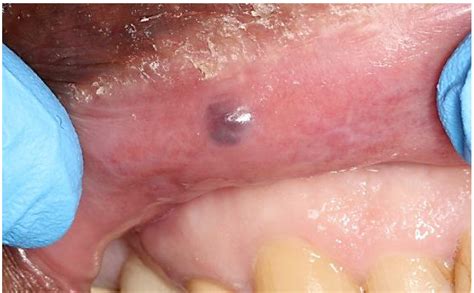

Melanoma

Melanoma is a type of skin cancer that can occur in the mouth, including the cheeks. It often appears as a dark spot or patch that may be asymmetrical, have irregular borders, and vary in color. Melanoma can be life-threatening if not treated promptly, so it is essential to consult a healthcare professional if you notice any suspicious spots.